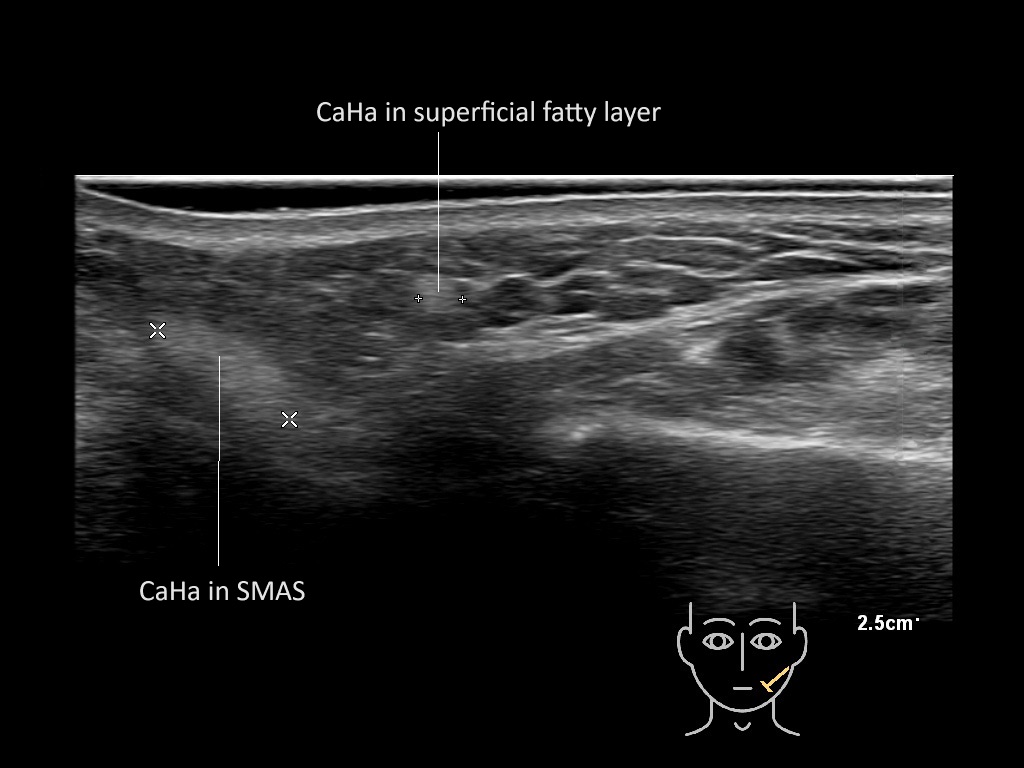

Filler deposits may end up unintentionally in the SMAS or fascial layers of the skin. Very often this will not lead to adverse events, however, adverse events ( nodules, migration / redistribution impaired muscle movement and smiling and malar edema) are are often related to filler ending up in the SMAS or fascia.

Study the first image to recognize the different layers. If you are sure about the layers, swipe to the second image to view the answer (if applicable).